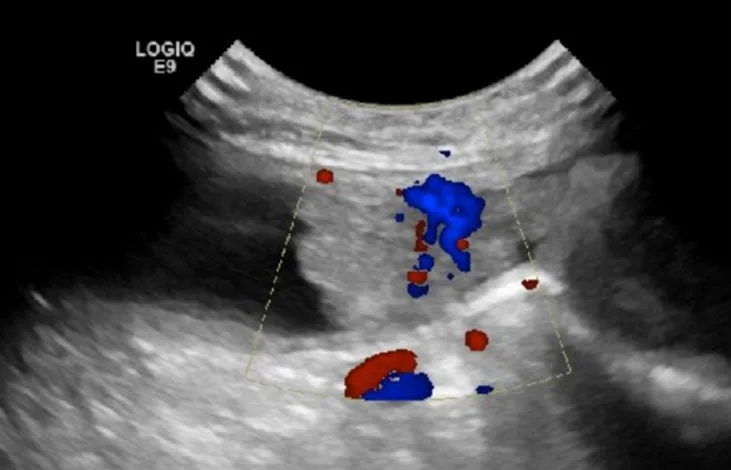

Patients with chronic polypoid cystitis (Figure 2) can also have multiple projections of soft tissue into the lumen of the urinary bladder. Identification of these protrusions and histopathology, in addition to clinical signs of recurrent UTI or results of traumatic catheterization, are needed to differentiate polypoid cystitis and neoplasia.

Sagittal image of the urinary bladder with soft tissue extending into the lumen, indicating a presumed polyp in a 12-year-old spayed bichon frise crossbreed. Color flow Doppler shows the single vessel extending into the lesion. Left, cranial; bottom, dorsal